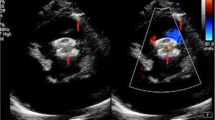

The heart was approached via a median sternotomy or a subxyphoid minimally invasive incision without sternotomy. Under continuous transesophageal echocardiography (TEE) guidance, the best location for right ventricular (RV) puncture was chosen, paying being attention away from any papillary muscles but far enough from the septum so as to approach it from a perpendicular angle with the needle and wire (Fig. 1). A 5-0 polypropelene purse-string was placed at the chosen location. An 18-guage needle (Cook, Bloomington, IN, USA) was introduced into the RV cavity and a 0.035-in. angled glide wire (Boston Scientific, Medi-Tech, Natick, MA, USA) was passed through the needle and manipulated into the left ventricular (LV) cavity through the defect. A 7- to 10-Fr short (8-13 cm) introducer sheath with a dilator was fed over the wire and carefully advanced into the LV cavity. Care must be taken to keep the tip of the dilator in the middle of the LV cavity (monitored by TEE) because it could perforate the LV free wall. The dilator was removed and the sheath tip positioned in the LV cavity. The appropriate device size was chosen to be 1 or 2 mm larger than the VSD size as assessed by color doppler TEE. The device was presoaked in nonheparinized patient’s blood for 10 minutes to allow for the tiny fenestrations of the nitinol mesh to thrombose. The device was then screwed to the cable and pulled inside a 6- to 9-Fr loader under blood seal to prevent any air bubbles. The device was advanced inside the short delivery sheath until it was seen by TEE to be close to the tip of the delivery sheath. The LV disc was deployed in the mid-LV cavity by gentle retraction of the sheath over the cable. The entire assembly (cable/sheath) was withdrawn gently until the LV disc was against the septum. Further retraction of the sheath over the cable would deploy the waist inside the septum. Continuous TEE to confirm the device position is of extreme importance. Once the position was confirmed, further retraction of the sheath to expand the RV disc was performed. If the device position was satisfactory, the device was released by counterclockwise rotation of the cable using the pin vise. A complete TEE study in multiple planes was done to confirm device placement and assess for residual shunting and any obstruction or regurgitation induced by the device.

(A) Four-chamber view of a mid- to posterior muscular ventricular septal defect (VSD) via intraoperative transesophageal echocardiography (TEE). LA, left atrium; LV, left ventricule; RA, right atrium; RV, right ventricule. (B) Color Doppier flow across the VSD. (C) Using a forceps tip, the right ventricular free wall is probed to determine the shortest distance from the free wall to the VSD, staying away from the anterior papillary muscle of the tricuspid valve. (D) A needle is introduced into the right ventricular cavity and a guidewire manipulated into the left ventricle. (E) An introducer sheath is passed over a dilator and positioned into the left ventricular cavity. (F) The device is pushed into the sheath and the LV disc deployed by gently retracting the sheath. (G) The RV disc is similarly deployed, but the device is still attached to the delivery cable. This allows for TEE confirmation of valve function and VSD closures, as well as recapture of the device into the sheath (by advancing the sheath), necessary. (H) Final confirmation of lack of shunting.